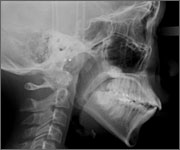

Diagnostic orthodontic records usually comprise: a panoramic x-ray, a cephalometric (head) x-ray, study models and digital photographs. These diagnostic records collectively enable Dr. Lee to develop an appropriate treatment plan specifically for you. Once all the diagnostic information is collected and reviewed then Dr. Lee thoroughly goes over the entire case.